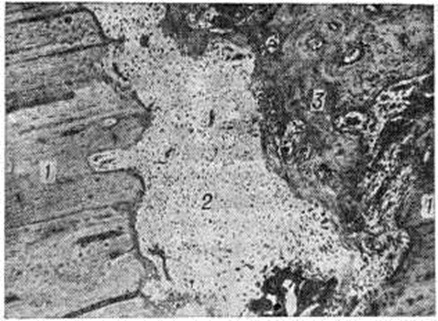

При точном сопоставлении отломков возможно прямое костное сращение с помощью интермедиарной костной мозоли, что именуют первичным костным сращением. Когда сращение отломков наступает после предварительного соединения их костно-хрящевой провизорной мозолью, на основе которой постепенно будет формироваться окончательная интермедиарная костная мозоль, говорят о вторичном костном сращении. Первичное костное сращение может произойти только в строго определённых условиях: при достаточном кровоснабжении отломков, точности их сопоставления, достаточности их обездвижения. Микрофотографии кости при первичном сращении в разные сроки консолидации представлены на рисунок 1 и 2.

Рис. 1.

Микропрепарат зоны костного сращения предельно сближенных отломков губчатой костной ткани метафиза через 2 недели после перелома. Контуры сросшихся отломков не определяются: 1 — старые костные пластинки; 2— новообразованные костные пластинки из не вполне зрелой костной ткани, окружающие старые; 3— межбалочные пространства с остеобластической тканью и сосудистыми капиллярами; окраска гематоксилин-эозином; × 20.

Рис. 2.

Микропрепарат участка сращения отломков компактной костной ткани (1) диафиза через 3 месяца после перелома: видна зрелая интермедиарная костная мозоль (2); окраска гематоксилин-эозином; × 75.

Рис. 3.

Микропрепарат участка диафиза кости через 2½ месяца после перелома: фиксация отломков (I) компактного вещества кости недостаточная, видна интермедиарная хрящевая мозоль (2) с очагом энхондрального окостенения (3); окраска гематоксилин-эозином; × 20.